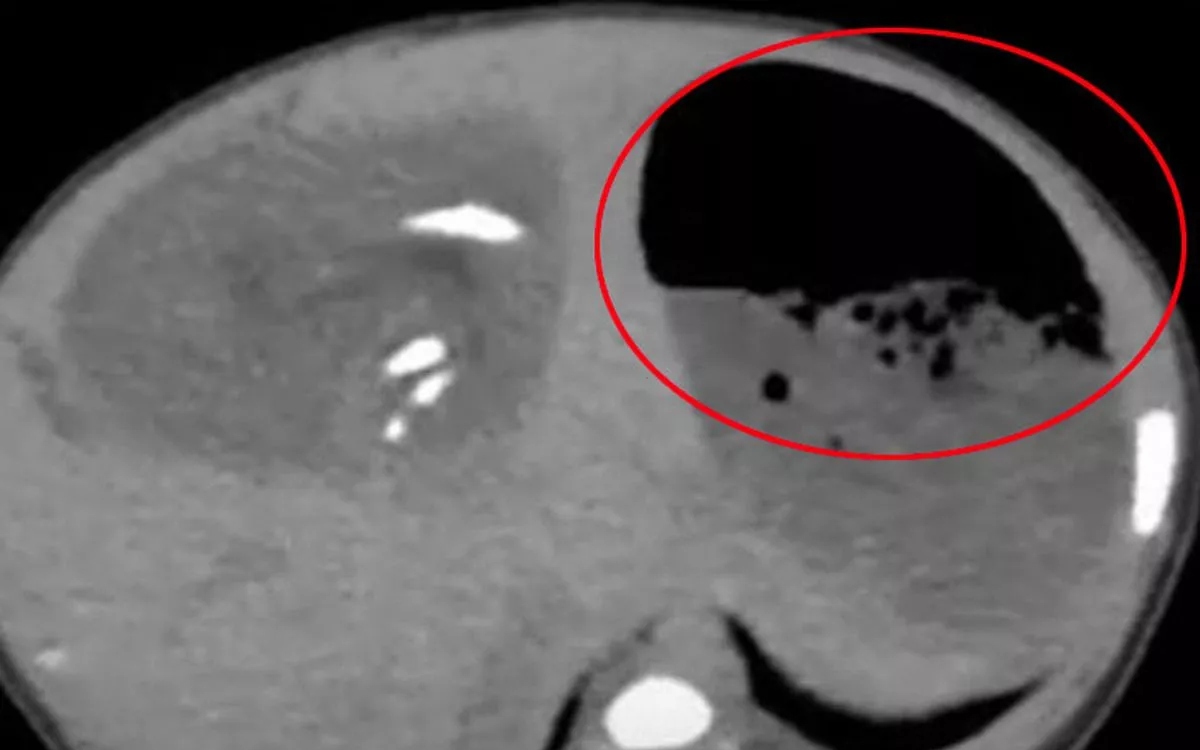

Bệnh nhi được chỉ định nội soi cấp cứu, phát hiện dị vật là một viên pin cúc áo. Các bác sĩ nhanh chóng lấy dị vật ra an toàn, tuy nhiên niêm mạc thực quản của trẻ đã bị tổn thương do phản ứng ăn mòn điện - hóa học.

Theo các bác sĩ, pin cúc áo tuy nhỏ nhưng cực kỳ nguy hiểm. Khi nuốt phải, chỉ trong vài giờ, pin có thể gây bỏng, loét, thủng thực quản hoặc khí quản, dẫn đến tử vong hoặc để lại di chứng nặng nề như hẹp thực quản, rò khí - thực quản, suy dinh dưỡng mạn tính.